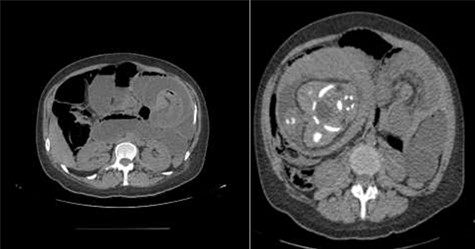

Physical examination presented normal vital signs. The abdomen was tender but lacked signs of peritonitis. Blood analysis revealed leukocytosis, neutrophilia and elevated lactate dehydrogenase. Obstetric ultrasonography (US) showed: fetus at cephalic presentation with good vitality, regular amniotic fluid volume, placenta without detachment. An abdominal computed tomography (CT) scan revealed proximal jejunal dilation caused by an ileoileal invagination and collapsed distal ileum (Figs 1 and 2). Betamethasone and atosiban were administered, and a supraumbilical laparotomy was performed. The intussusception in the common limb (80 cm distal to jejunojejunostomy) (Fig. 3) was reduced (Figs 4 and 5) with progressive and complete intestinal vascular perfusion (Fig. 6). The postoperative period was uneventful, and a caesarian was performed 4 weeks later. At the 45-month follow-up, there was no recurrence.

Axial view of the CT scan showing jejunojejunal intussusception with fat and blood vessels within the lumen of intestine (white arrow—typical “target sign”).